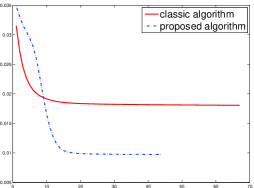

In order to compare the convergent speed of the proposed algorithms with the classic algorithms visually, we present the evolution of MSE along with the iteration process in Fig. 4 for the 3 projection data. And we can observe that the proposed perturbation can accelerate the convergent rate and improve the reconstructed image qualities.